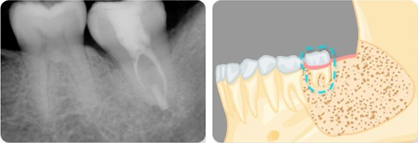

매복치로 인해 영구치 뿌리가 흡수되었을 경우

같은편의 제2대구치는 건강하나 제1대구치의 손상이 심한 경우